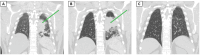

This case report depicts two patients with morbid obesity who presented to the ED with signs and symptoms of community-acquired pneumonia and were treated accordingly. Despite empiric antibiotic therapy, their symptoms did not subside, prompting further evaluation, which revealed pulmonary blastomycosis. Both patients were also found to have severe vitamin D deficiency. Treatment with amphotericin B followed by itraconazole, along with aggressive vitamin D supplementation, led to clinical improvement and resolution of lung lesions in both cases. Although blastomycosis is not rare in immunocompetent individuals, its severe forms are usually associated with underlying immunosuppression or significantly high inoculum. Blastomycosis presents a diagnostic challenge due to its nonspecific symptoms and radiographic findings. This case series underscores the importance of considering blastomycosis in the differential diagnosis of persistent pneumonia in obese individuals, particularly in endemic areas. It also suggests that vitamin D deficiency may play a role in disease susceptibility and severity. This report contributes to existing medical literature by emphasizing the potential link between obesity, vitamin D deficiency, and the risk of blastomycosis, highlighting the need for further research into this association.